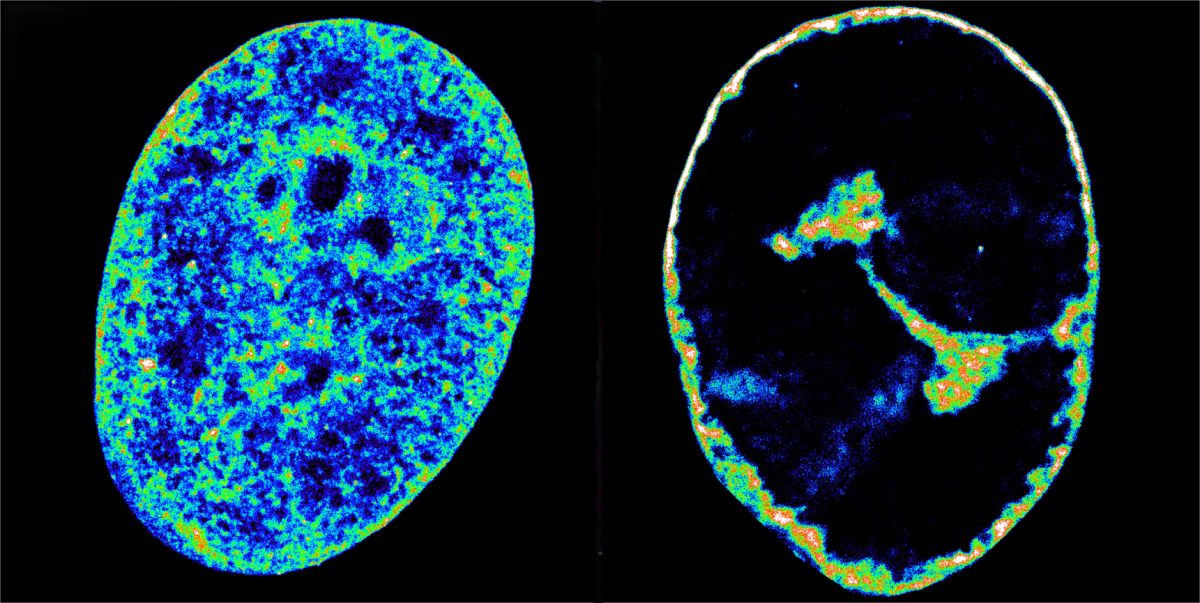

Los científicos del CRG descubrieron que el virus del herpes labial remodela la arquitectura del genoma humano, reorganizando su forma en el espacio tridimensional para que el VHS-1 pueda acceder a los genes del huésped más útiles por su capacidad de reproducción.

Si bien se vió que otros virus del herpes compactan y remodelan los cromosomas del huésped, no estaba claro si era un efecto secundario de la invasión del virus y la creación de sus propias fábricas de replicación viral. El estudio es la primera prueba que demuestra que el VHS-1 remodela el genoma humano deliberadamente y a las pocas horas de la infección.